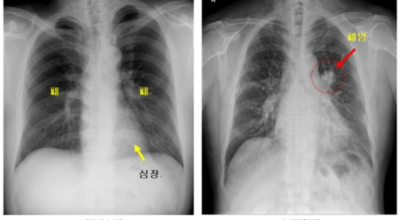

폐암 검사는 X-ray를 통해서 검사하는데 , 크기가 작거나 구석에 위치한 경우 확인이 어려운 경우도 있답니다. 그리고 조직 검사를 통해서 정확한 진단을 하게 되어요. 폐암이 발견되면 종양의 크기나 전이 여부 , 위치에 따라서 수술 여부를 결정하게 되어요.